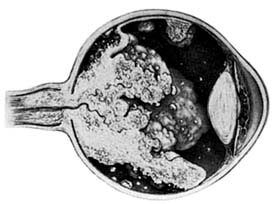

Retinoblastoma (Figure 10-32)

Figure 10-32

Figure 10-32: Retinoblastoma as viewed through the pupil.

Retinoblastomas may exhibit outward (exophytic) or inward (endophytic) growth-either or both. The latter then extend into the vitreous (Figure 10-33). Both types gradually fill the eye and extend through the optic nerve to the brain and, less commonly, along the emissary vessels and nerves in the sclera to the orbital tissues. Occasionally, they grow diffusely in the retina, discharging malignant cells into the vitreous or anterior chamber, thereby producing a pseudoinflammatory process and mimicking retinitis, vitritis, uveitis, or endophthalmitis. Microscopically, most retinoblastomas are composed of small, closely packed, round or polygonal cells with large, darkly staining nuclei and scanty cytoplasm. They sometimes form characteristic Flexner-Wintersteiner rosettes, which are indicative of photoreceptor differentiation. Degenerative changes are frequent, accompanied by necrosis and calcification. A few will spontaneously resolve.

Figure 10-33

Figure 10-33: Endophytic retinoblastoma.